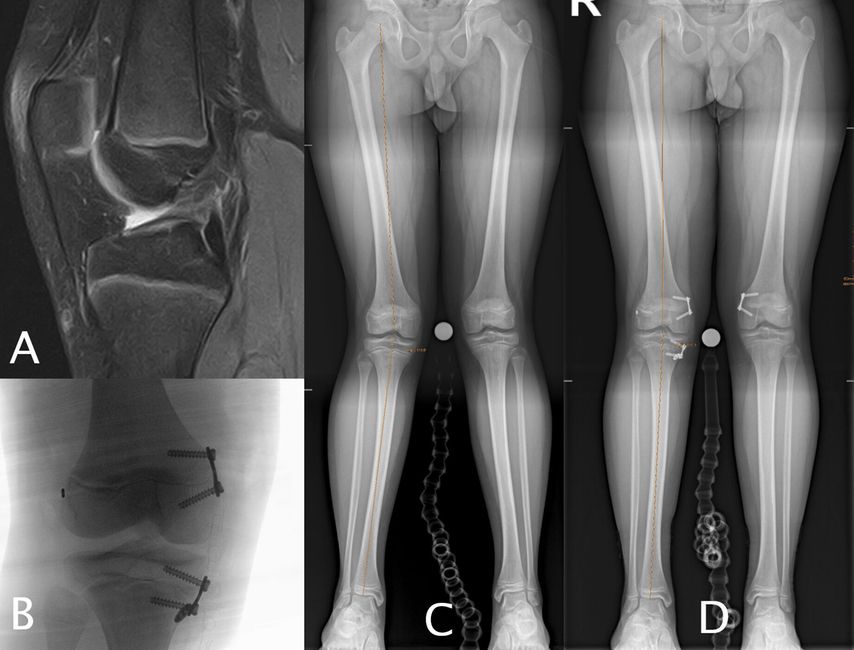

Abb. 2: 33-jährige ehemalige Leichtathletin mit einer primären VKB-Ruptur (A), deutliche Chondropathie im medialen Kompartiment, Varusfehlstellung von 9° primär aus dem distalen Femur resultierend (LDFA 92° [C]), behandelt mit einer einzeitigen CW-DFO und VKB-Plastik (4-Strang-Semitendinosus-Graft)